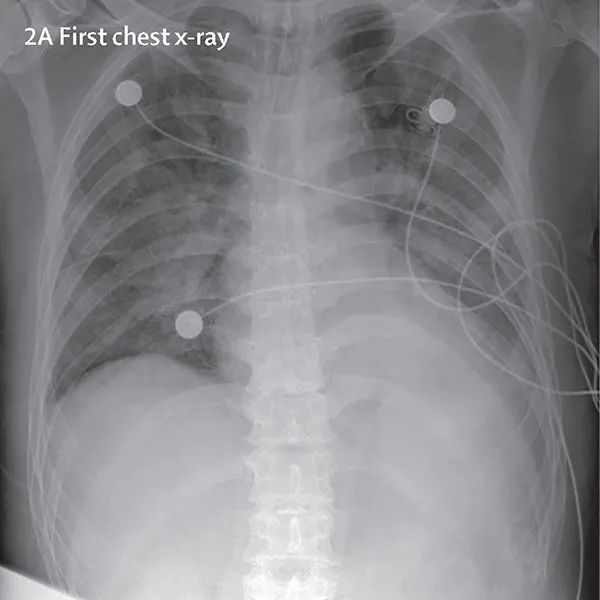

下图是一张COVID-19检测呈阳性病人的X光照片。利用X射线图像,我们可以使用Keras和TensorFlow来训练一个机器学习分类器,然后用它来检测COVID-19。由于COVID-19攻击人的呼吸上皮细胞,因此我们可以用X射线来检测病人肺部的健康状况。

左图:阳性样本;右图:阴性样本